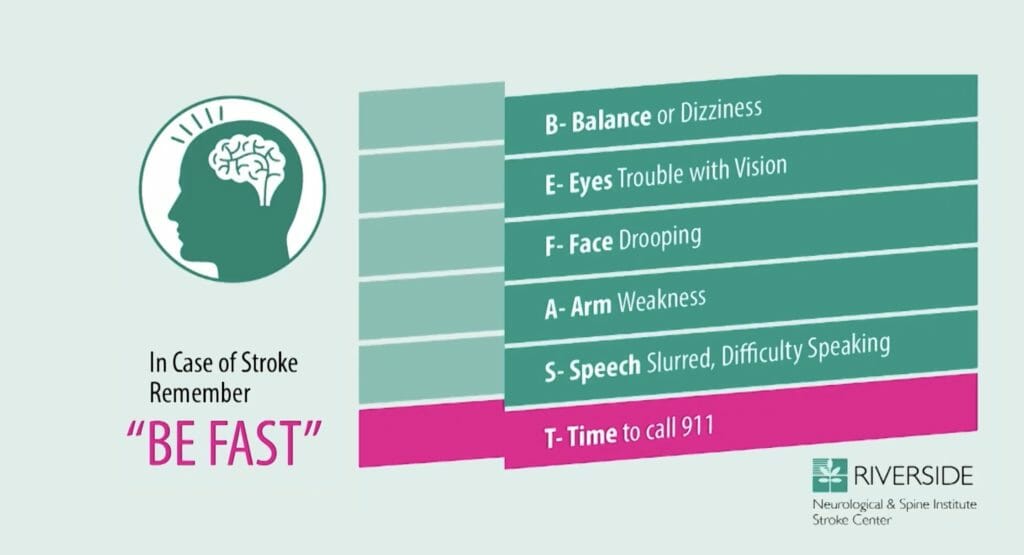

Symptoms of a stroke can range from very mild to severe. When it comes to symptoms of a stroke- remember the acronym BEFAST. Balance (or dizziness), Eyes (trouble with vision), Face drooping, Arm weakness, Speech slurred, Time to call 911!